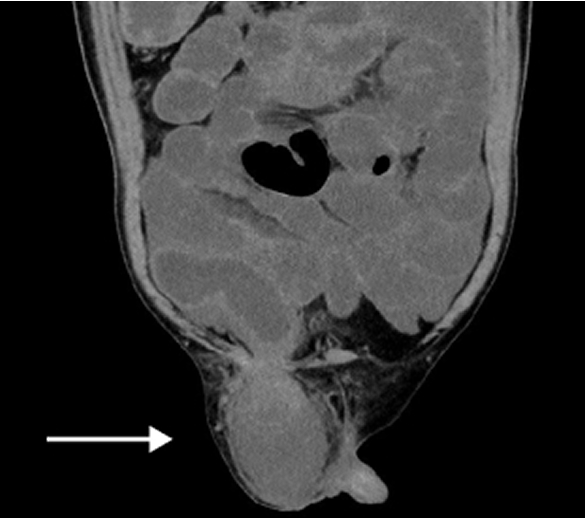

ソケイヘルニア(脱腸)の嵌頓では腸管(主に小腸)や内臓脂肪がヘルニア嚢内に脱出してヘルニア門に挟まれ元に戻らなくなった状態になります。

特に腸管の場合には、腸内の流れが遮断されて腸閉塞になる場合や腸管の血行が遮断されると腸管壊死を起こすことがあります。腸管を切除せざるを得ない場合には治療に時間を要する可能性があります。

腸管を温存できた場合も多くの場合、図のように嵌頓を解除した腸管にダメージを追っており、慎重な術後管理が必要となります。